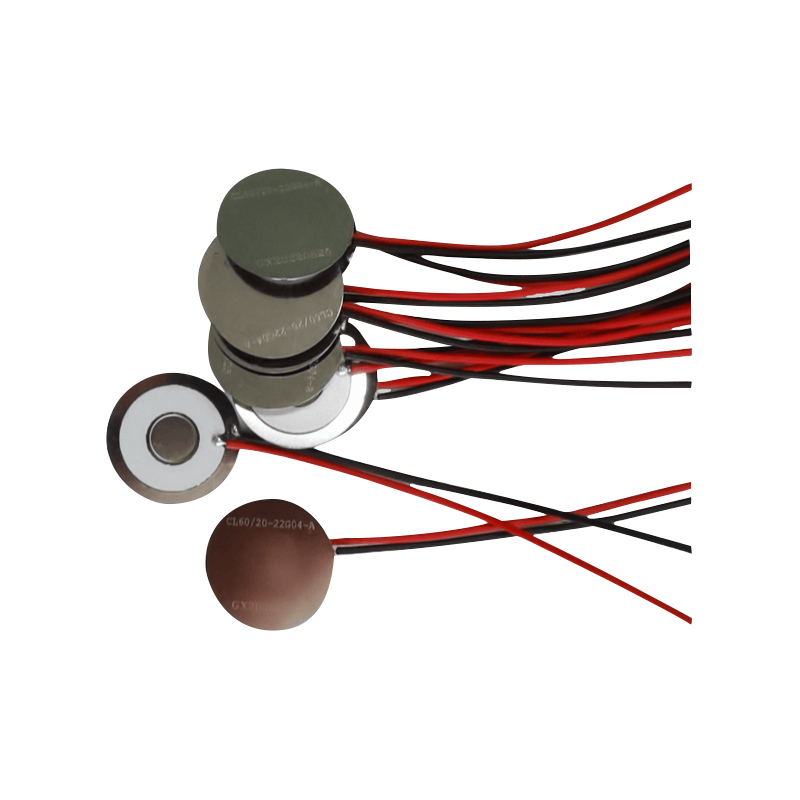

Les comprimés de nébuliseur à mailles médicales sont des composants de précision utilisés dans les dispositifs médicaux pour convertir des médicaments ou des solutions en minuscules particules d'aérosol pour le traitement de divers troubles respiratoires tels que l'asthme et la maladie pulmonaire obstructive chronique (MPOC), etc. par inhalation. La conception et le choix des matériaux de la feuille du nébuliseur sont essentiels pour garantir une administration efficace du médicament et le confort du patient. La feuille de diaphragme en acier inoxydable est percée de milliers de minuscules trous de maille de 2 à 3 µm dans la tôle d'acier grâce à une technologie de perçage laser dans un processus laser de précision, puis elle est étroitement liée à la feuille ronde en céramique piézoélectrique, qui convertit la fréquence de résonance de la feuille piézoélectrique en énergie de vibration haute fréquence via le signal de sortie de la carte de commande PCB, et décompose rapidement le médicament liquide en fines particules d'aérosol. Ces gouttelettes sont également appelées taille médiane des particules. Lorsque le pourcentage médian de la taille des particules D50 atteint > 60 % ou plus, les particules seront suffisamment petites pour pouvoir atteindre profondément les poumons jusqu'à la surface des alvéoles avec la respiration, améliorant ainsi l'efficacité d'absorption du médicament et l'effet thérapeutique. La feuille de nébuliseur à micro-mailles médicales a principalement plusieurs formes, une feuille de nébuliseur à micro-mailles en acier inoxydable, une feuille de nébuliseur médical en nickel palladium, une feuille de nébuliseur médical en polymère PI, etc. Tout ce qui précède se fait grâce à la conversion d'énergie de vibration piézoélectrique en céramique pour obtenir l'effet d'atomisation.

La céramique piézoélectrique sans plomb est connue sous le nom de « perle » de l'industrie piézoélectrique. L'avenir remplacera progressivement la céramique piézoélectrique à base de plomb sous tous ses aspects, qui a déjà les mêmes performances piézoélectriques, et la feuille piézoélectrique à base de plomb. Il est totalement non toxique, inoffensif, sûr et respectueux de l'environnement, ne contient pas de plomb, d'antimoine et d'autres métaux lourds et autres éléments restreints par Rohs, température de Curie élevée Tc-328 ° C, très faible perte électrique TangentLoss Par conséquent, la puce d'atomisation médicale piézoélectrique sans plomb a une grande valeur commerciale et une valeur universelle, des céramiques piézoélectriques véritablement non toxiques et respectueuses de l'environnement, sans plomb, en plus de performances piézoélectriques non polluantes comparables à celles des céramiques à base de plomb, deviendront une céramique piézoélectrique respectueuse de l'environnement populaire. Après des années de recherche et de développement, après des tests et des expérimentations continus, la société a réussi à fabriquer la puce d'atomisation médicale sans plomb pour atteindre le même niveau d'atomisation que la puce d'atomisation à base de plomb et les mêmes exigences en matière de particules de diamètre. La puce de nébuliseur Mesh médical sans plomb brillera sûrement et obtiendra un large éventail de scénarios d'utilisation.

L'atomiseur à ultrasons est un appareil qui utilise le principe de vibration ultrasonique (conversion d'énergie) pour convertir le liquide en minuscules gouttelettes. Le principe de fonctionnement est que les propriétés piézoélectriques uniques de la céramique piézoélectrique de la décision, la pièce d'atomisation à la réception de l'excitation du signal de champ électrique correspondant, produira la fréquence d'oscillation correspondante, grâce au rôle de vibration à haute fréquence de la cavitation liquide rejetée de la surface de l'eau pour produire une sorte de particules de brouillard d'eau, atomisées avec un grand nombre d'ions négatifs et de petites particules de molécules, peuvent réaliser une augmentation de l'humidité ambiante, le rôle de l'air frais. La surface de l'atomiseur est recouverte d'émail vitreux à une température élevée de 800 degrés pour protéger les électrodes d'argent de la feuille piézoélectrique, augmenter la résistance aux acides et aux alcalis et la résistance à l'oxydation de l'atomiseur et augmenter la durée de vie de l'atomiseur. Largement utilisé dans les humidificateurs d'intérieur, les purificateurs d'air, le traitement par nébuliseur médical et les voitures de beauté, par exemple dans d'autres domaines, mais convient également aux entrepôts, aux usines, à l'humidification, à la désinfection, pour créer l'atmosphère des équipements d'humidification. Les comprimés de brumisation sont principalement utilisés dans l'humidification industrielle, la brumisation médicale, la brumisation d'aromathérapie, l'humidification environnementale, la brumisation de jardin et d'autres scènes.